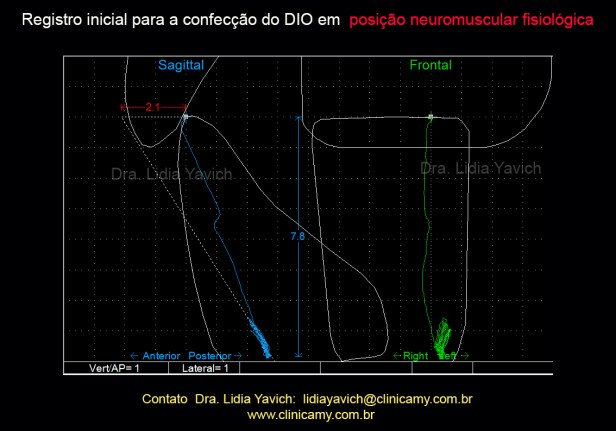

Os músculos mastigatórios da paciente foram desprogramados eletronicamente e uma nova posição neurofisiológica de repouso foi registrada.

A paciente apresenta um espaço livre patológico de 5, 8 mm, já descontado os dois mm fisiológicos de um espaço livre sadio.

A paciente também apresenta uma retroposição de 2,1 mm

Com esses dados construímos um DIO (dispositivo intraoral), para manter tridimensionalmente a posição registrada. Este dispositivo deve ser testado eletromiograficamente para mensurar objetivamente o paciente.

Com esses dados construímos um DIO (dispositivo intraoral), para manter tridimensionalmente a posição registrada. Este dispositivo deve ser testado eletromiograficamente para mensurar objetivamente o paciente.